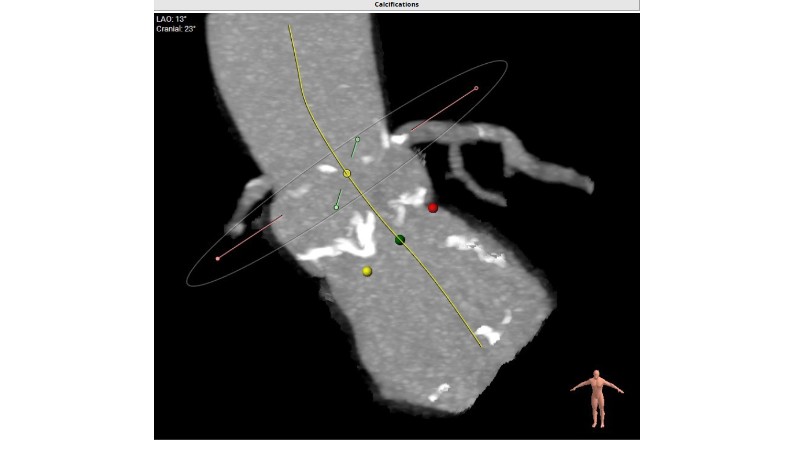

Discover how thoughtful index valve selection and implantation techniques can shape the long-term management of patients undergoing TAVI. This PCR London Valves 2025 session highlights treatment considerations for low- and intermediate-risk patients, explores how valve choice affects the feasibility of future interventions, and examines strategies to achieve optimal and durable clinical outcomes. Follow real patient case with imaging analysis, hemodynamic insights in small annuli, and discussions on planning for future revalving and coronary access.